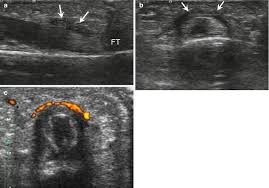

Imaging Of Rock Climbing Injuries Radiology Key

Imaging Of Rock Climbing Injuries Radiology Key from radiologykey.com

There are 2 musculotendinous units that could be involved, the flexor digitorum superficialis (fds) and flexor digitorum profundus (fdp). The moment arm of the fdp tendon over the pip joint has thus increased by 3 per cent. Surgery is often necessary to repair complete tendon tears. Five flexor tendon zones were described based on anatomy that help dictate treatment principles ( fig. Flexor tendon pulley injuries in rock climbers closed pulley ruptures are rare in the general population but occur more frequently in rock climbers due to biomechanical demands on the hand.

Endurance climbing typically involves spending a longer time on the wall pulling less hard, and in the case of tendon rehab, it is a safer way to climb when getting back on the wall. Flexor tendon pulleys (we will focus on the annular pulleys), named a1 through a5, act as a ligamentous strap to keep the tendon in close contact with the phalanges.the best analogy for this is a fishing rod. Approximately three climbing routes have to be negotiated in order to perform 100 moves, to warm up, and be ready for maximum loads in the region of the flexor tendon sheath 8. Tenosynovitis, or inflammation of the finger flexor tendon sheath (synovium), is a common overuse syndrome that climbers may experience. Generally if something isn't hurting your finger, it isn't making it worse. A good understanding of the treatment procedures, healing. Five flexor tendon zones were described based on anatomy that help dictate treatment principles ( fig. The most important, and also the most commonly injured, being a2 and a4.